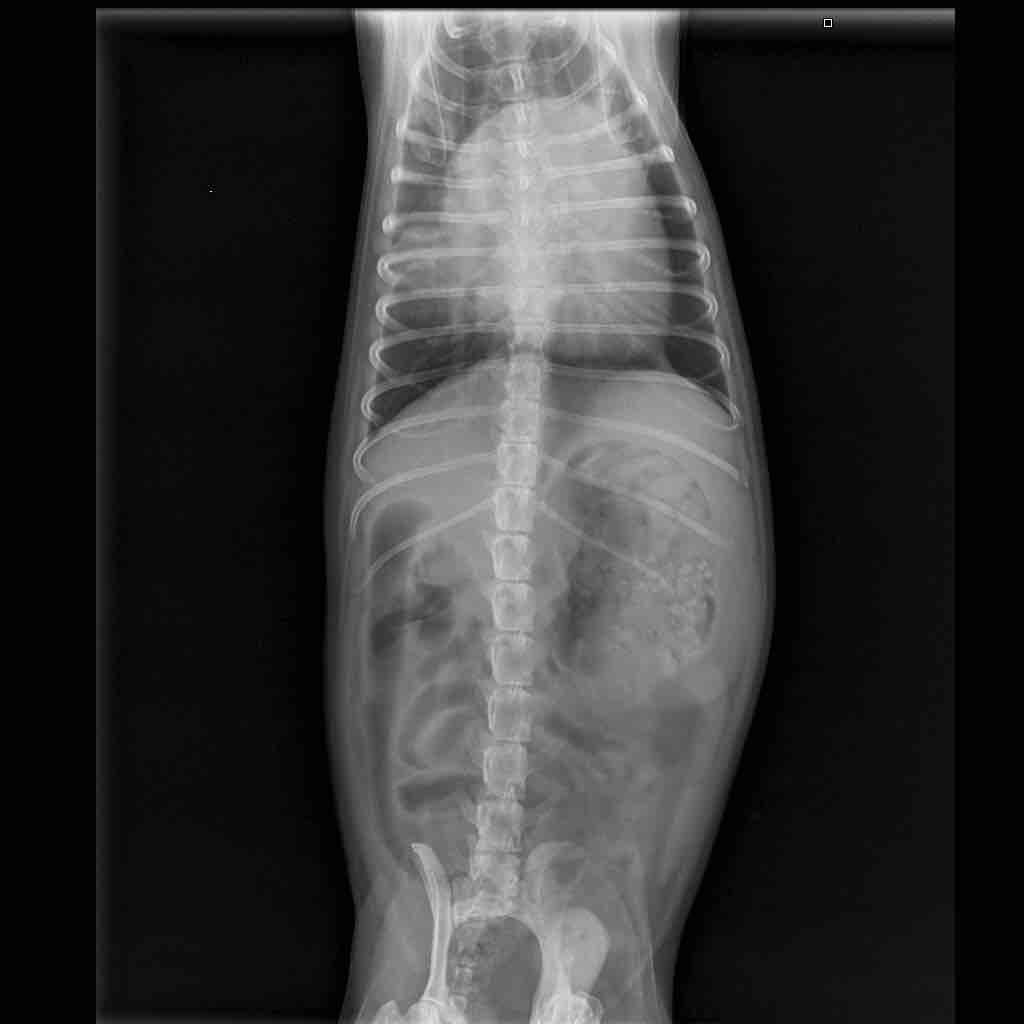

My dog is suffering from enlarged spleen. His lower stomach is a bit enlarged and he sneezes every once in a while. Also his breathing is a bit heavy and in some cases I can hear him trying to breath deeply two or three times in a row. Is there some medication to help him with the spleen issue? I cannot relay on vets in my current location as animal care is not that common to them

Enlarged spleens can occur for many reasons including immune mediated disease, infections and tumours and the treatment for each is quite different. Blood tests to rule out infections and removal and biopsy of the spleen are often used to investigate. There is no single treatment which would be expected to be curative but a well balanced diet is recommended